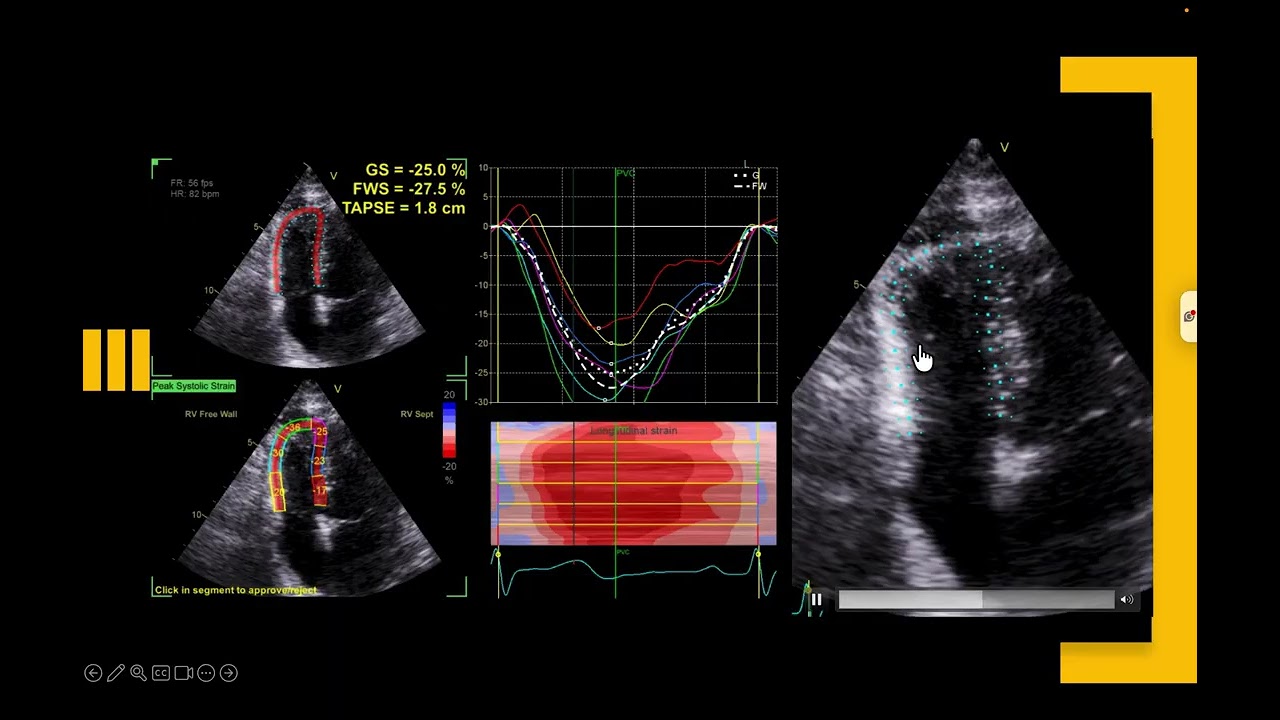

Moderator band is one of the criteria for naming a ventricle as right ventricle on fetal or congenital echocardiography. By this video i would share a caution.